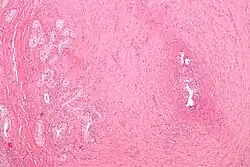

| Micrograph of vasitis nodosa (left of image). H&E stain. | |

Vasitis nodosa is a complication experienced in approximately 66% of men who undergo vasectomy.[1] It is a benign nodular thickening of the vas deferens, in which small offshoots proliferate, infiltrating surrounding tissue.[2] It can be mistaken for low-grade adenocarcinoma by pathologists,[3] and is implicated in late vasectomy failure.[2]